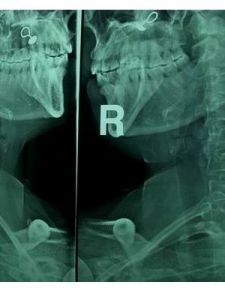

(3)x線片顯示椎間關節失穩或鉤椎關節骨質增生;